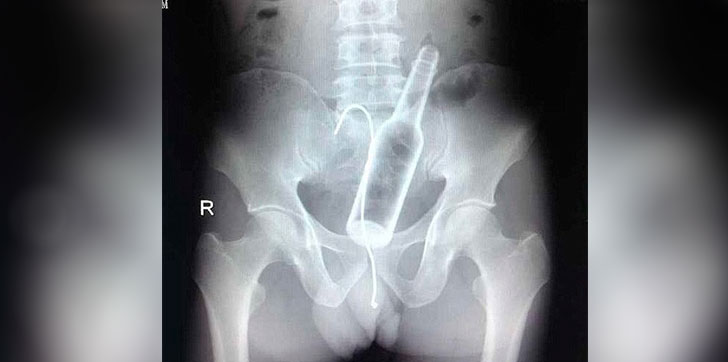

El tema surge a raíz de la publicación del paciente de 40 años de edad a quien médicos del hospital Francisco Moscoso Puello le extrajeron un frasco de metal en el tracto intestinal.

El director del Servicio Nacional de Salud (SNS), Chanel Rosa Chupany, informó que sancionará a las personas responsables de difundir, a través de las redes sociales, la imagen de la radiografía realizada al paciente. Afirmó que un médico residente de anestesiología es uno de los responsables.